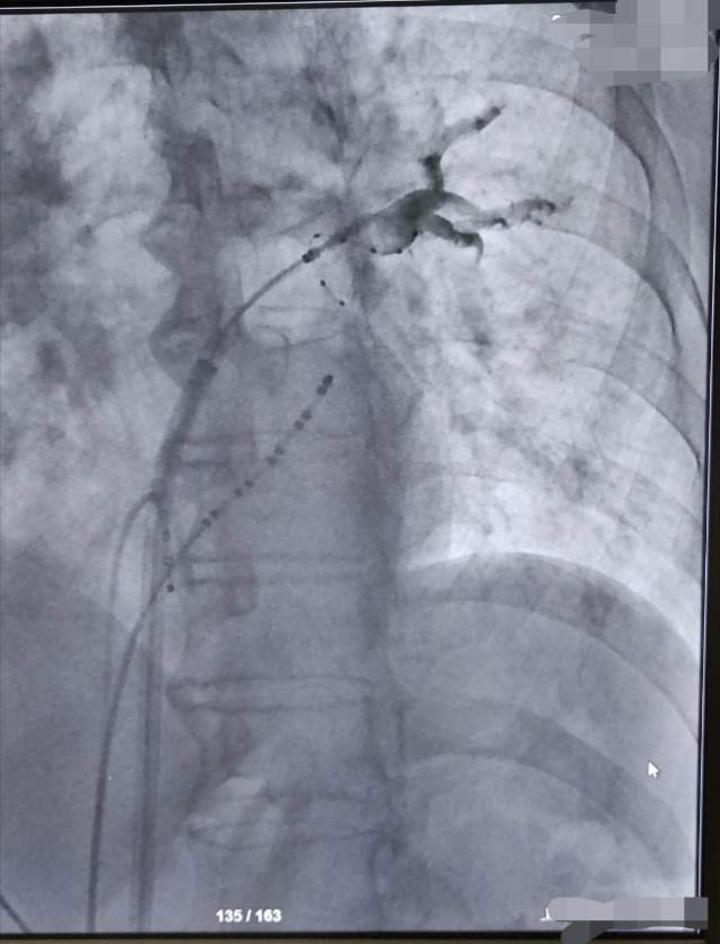

剪头所指,可以清楚看到肺静脉电位冷冻消融过程中消失。

让治疗效果可视化,实时监测。